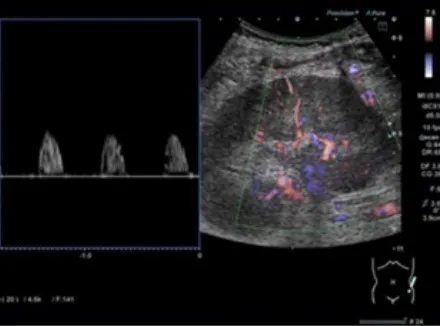

Hematúria e anormalidades em tomografia